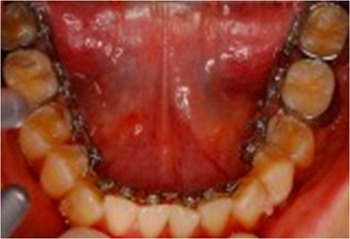

(1) 裏側矯正≪正式には舌側矯正(ぜっそくきょうせい)といいます≫

歯の裏に金具を付けてワイヤーで動かす方法で、装置はほとんど見えませんが自分では外せない固定式です。ほとんどどんな場合でも可能で、希望の形に完全に治せる事が多いです。治療費は症例によりますが40~130万円くらいです。期間は1~3.5年で月1回来院